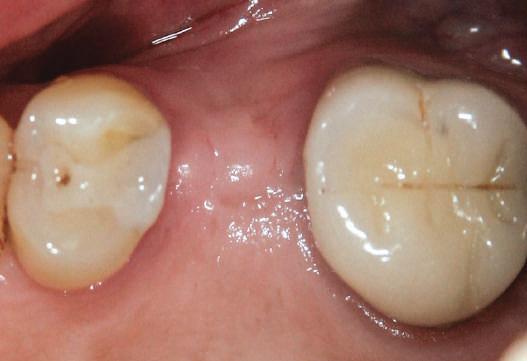

Fig. 1 prezintă pacientul după inserarea primului set de bonturi implantare individualizate; dinţii naturali adiacenţi

sunt încă prezenţi pentru a susţine puntea provizorie.

Cazul (1): Reprepararea intraorală a bonturilor Figurile

1. Aspect după inserarea primului set de bonturi implantare individualizate.